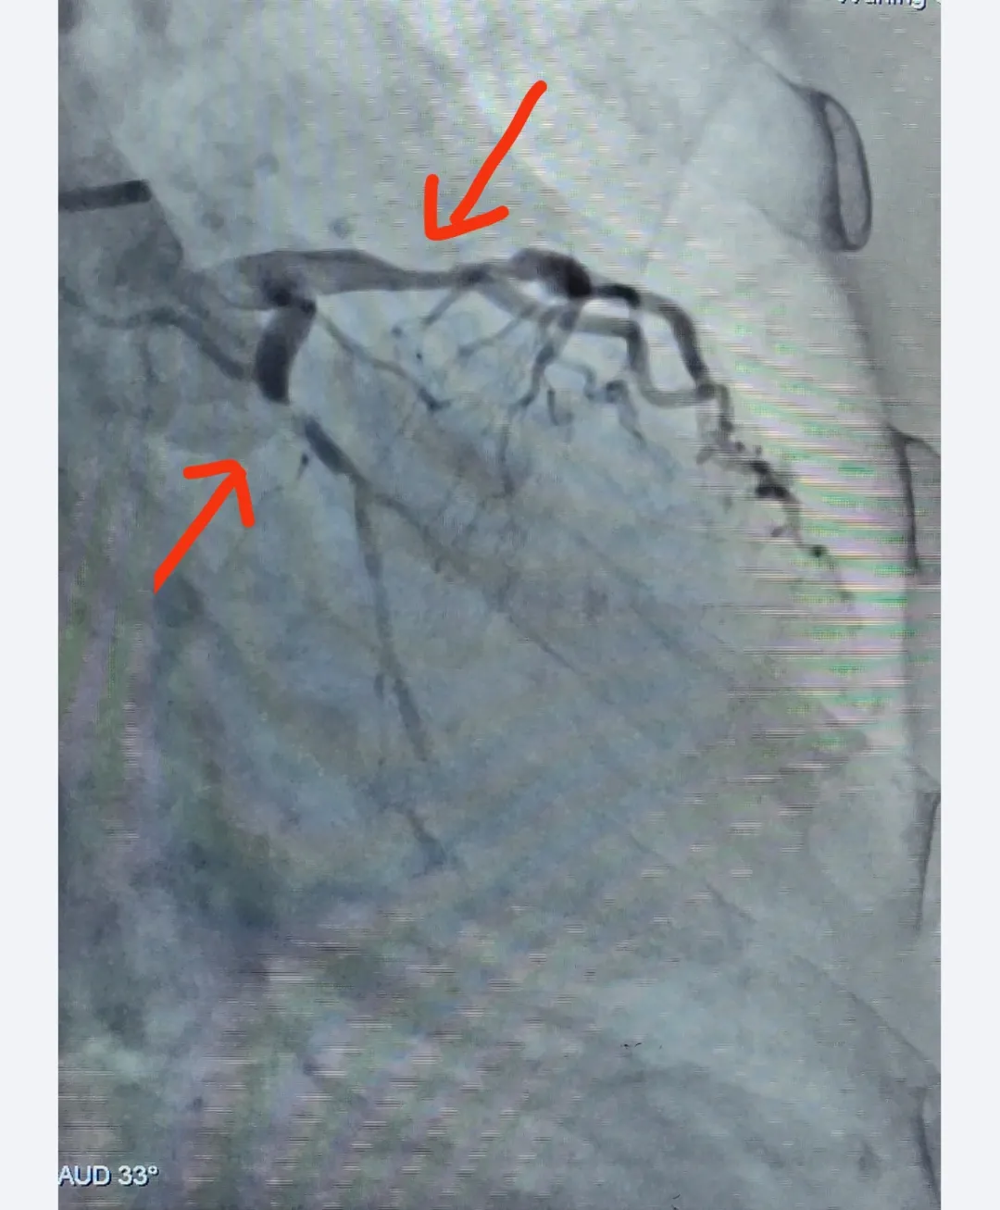

支架植入后